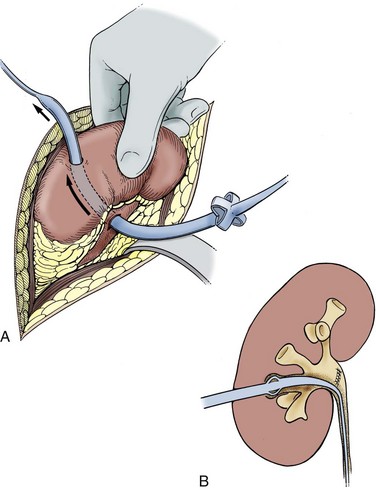

Intrarenal aneurysms are considered congenital and account for one fifth of aneurysmal disease affecting the kidney (Fig. 54–47). In some instances they may develop secondary to atherosclerosis, mural dysplasia, trauma, inflammation (arteritis), or needle biopsy. Intervention is warranted for lesions larger than 2 cm or those associated with hypertension. Lesions can rupture and dissect leading to ischemia or may contribute to thrombus formation and warrant intervention (revascularization or coil placement). Women in childbearing age with evidence of aneurysms are urged to undergo repair secondary to risk of rupture and associated high rates of maternal and fetal mortality (Figs. 54-48 and 54-49) (Yang and Hye, 1996; Centenera et al, 1998).

Figure 54–47 A, Large left congenital renal aneurysm and arteriovenous malformation. B, Note early filling of the renal vein and inferior vena cava.